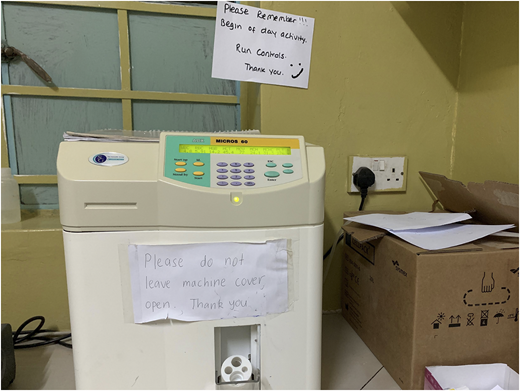

Performing QC for blood count analyzers

The rates of performing of quality control (QC) and preventive maintenance were low. So procedures were established that require daily QC; daily, weekly, and monthly preventive maintenance; and engineer servicing and documentation once every 6 months. A laboratory manual incorporating SOPs is also planned. A program for exchanging samples was arranged with the provincial Chipata Central Hospital Laboratory (Chipata, Zambia). Our laboratory staff were educated on the importance of performing QC. Data were collected retrospectively measuring documented QC completion in the hematology laboratory before the intervention (third quarter [Q3] and Q4 of 2018) and after the intervention (Q1 and Q2 until June 16, 2019) for blood count analyzers (Figure 7). Pearson’s χ2 test was applied to the data, and the result showed significant improvement in QC performance (P < .001) (Tables 5 and 6).

The importance of preventative maintenance and QC on the quality of laboratory results has been a point of focus at SFH. This photo shows our HORIBA ABX Micros 60 automated hematology analyzer used for in-vitro diagnostics testing of whole blood specimens.

The importance of preventative maintenance and QC on the quality of laboratory results has been a point of focus at SFH. This photo shows our HORIBA ABX Micros 60 automated hematology analyzer used for in-vitro diagnostics testing of whole blood specimens.